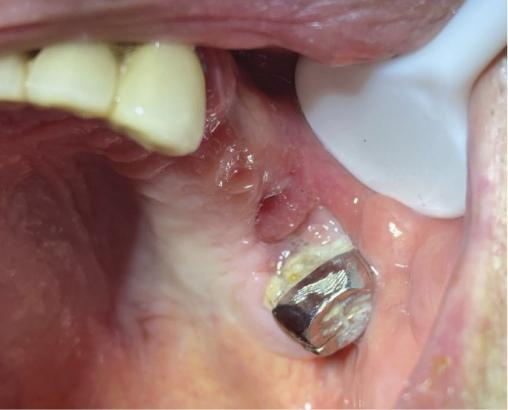

Le panoramique dentaire (fig. 1) met en évidence une solution de continuité de l’os alvéolaire au niveau de la dent 26 extraite. L’aspect est bourgeonnant (fig. 2). Un prélèvement histologique est effectué, qui montre une métaplasie malpighienne avec dysplasie de haut grade, sans infiltration du chorion, au niveau de la zone de jonction entre l’épithélium malpighien de surface et l’épithélium cylindrique cilié sinusien.